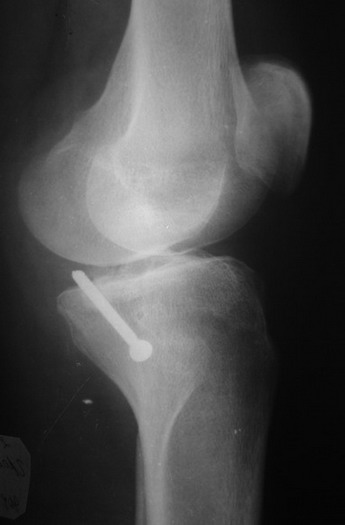

В  3  из  4  случаев  мы  применили  винт,  проведенный ретроградно по

аналогии с фиксацией заднего края большеберцовой кости при переломах в

области  голеностопного  сустава.  В прищепке рентгенограммы одного из

наших  пациетов  до  операции и спустя полгода. Остальные 3 наблюдения

Вложение не в текстовом формате было извлечено…

Имя     : 3.jpg

Тип     : image/jpeg

Размер  : 28123 байтов

Описание: отсутствует

Url     : http://weborto.net:8080/pipermail/ortho/attachments/20070808/782df48f/attachment-0005.jpg